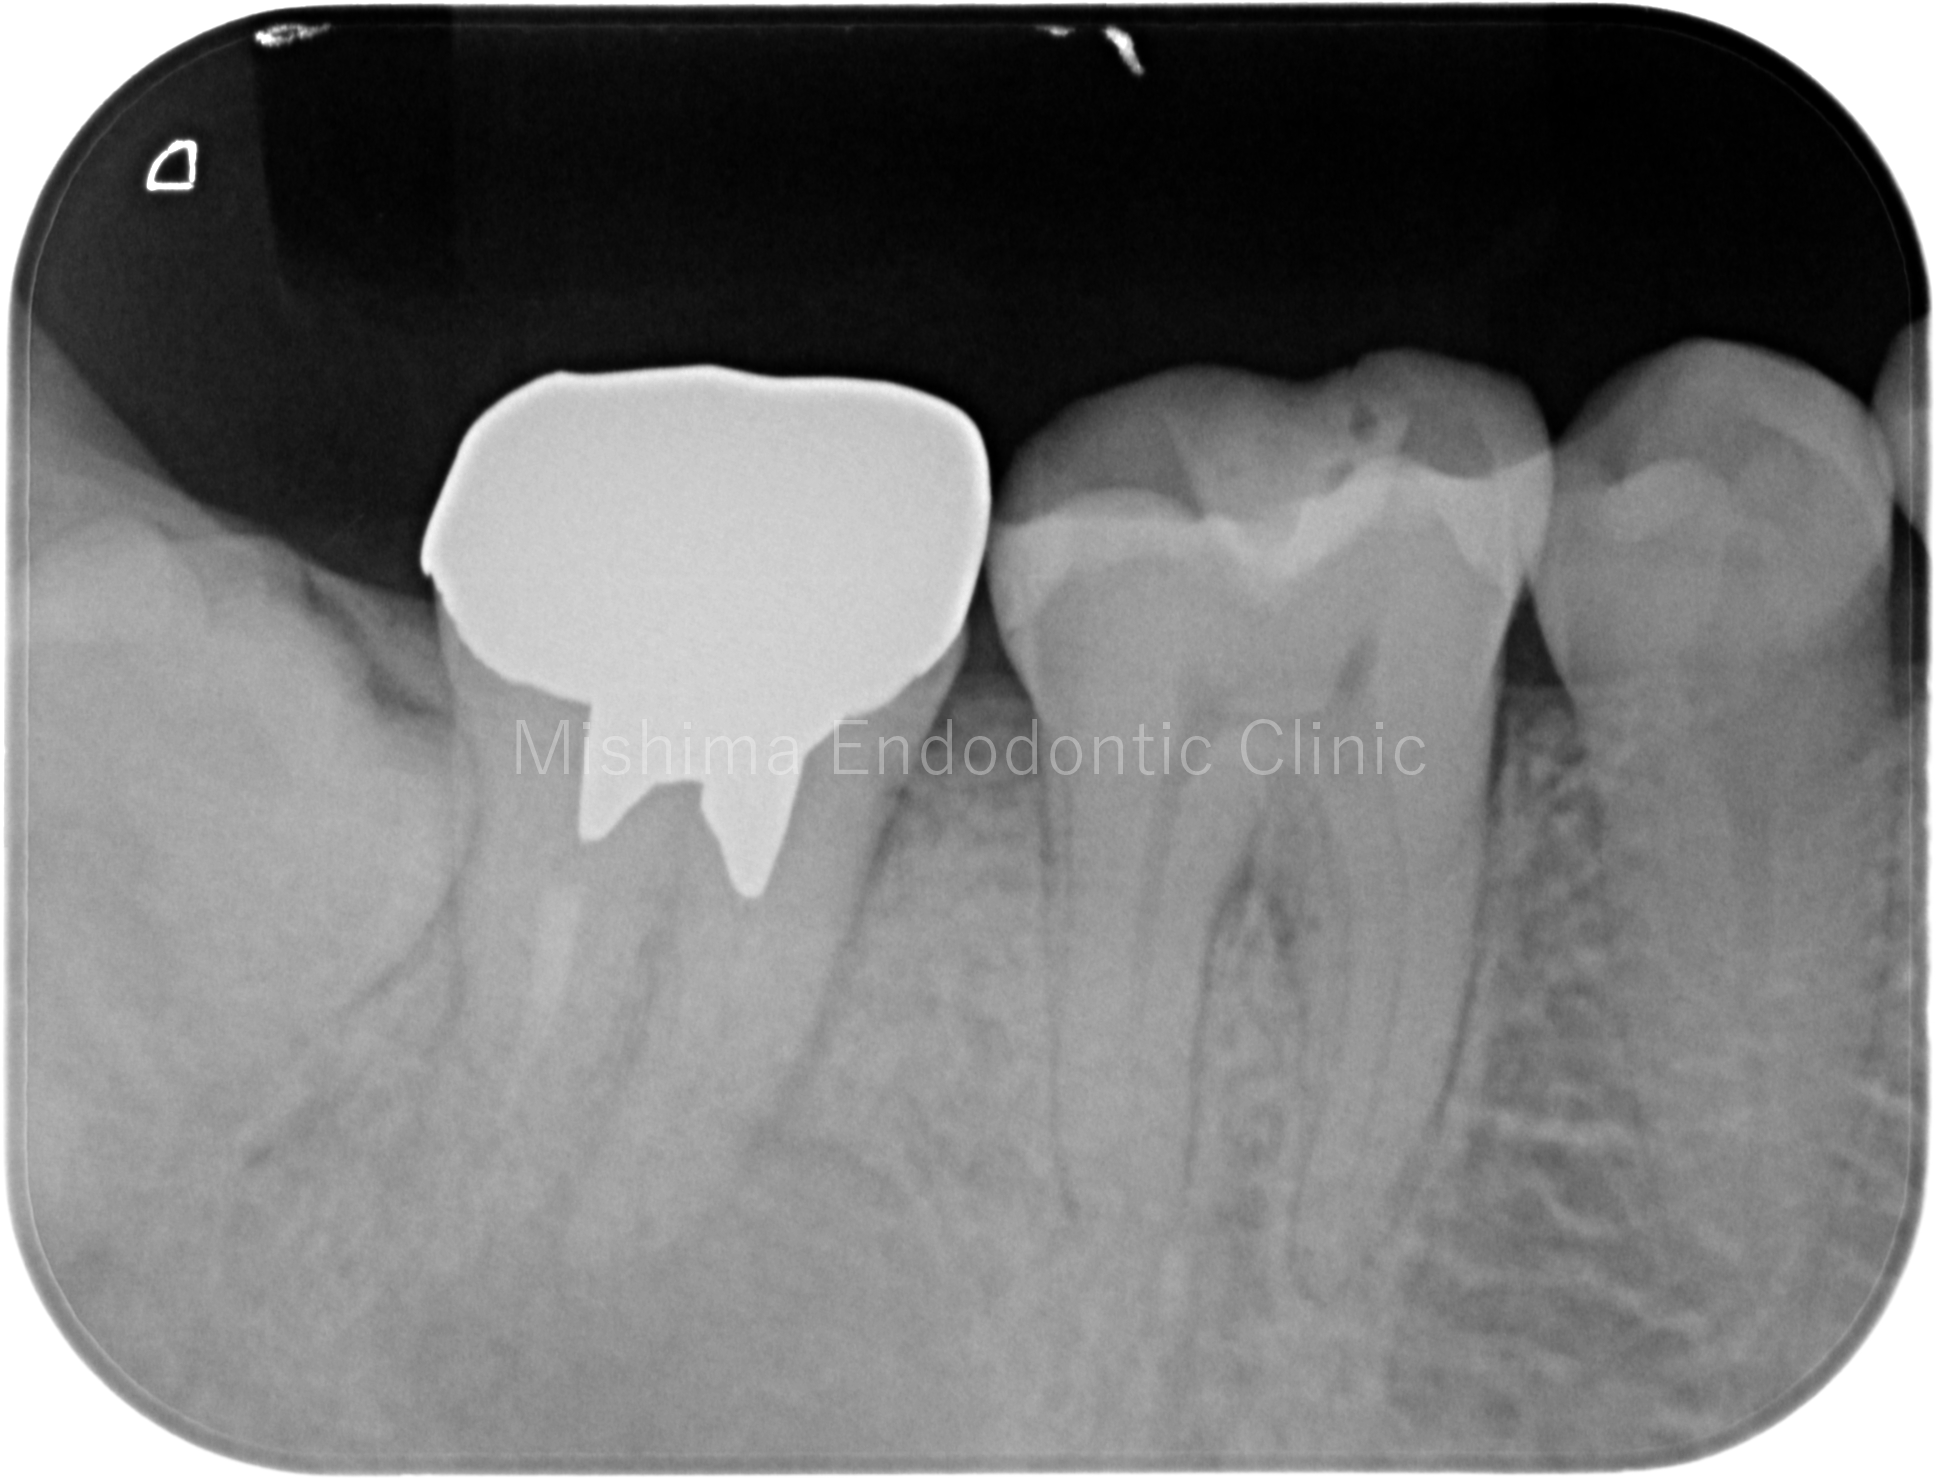

Before

術前